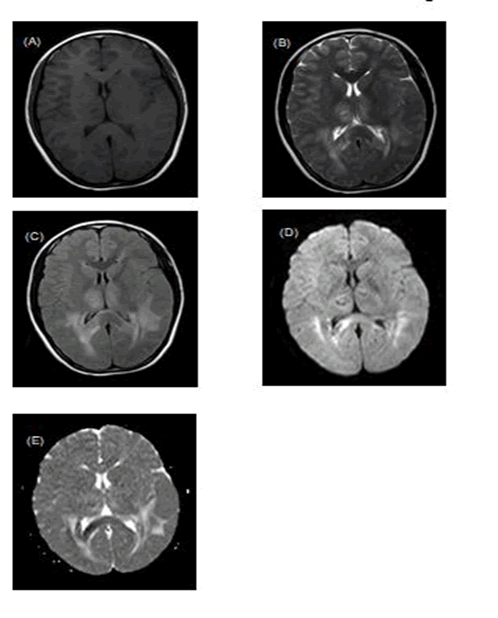

Laboratory workup revealed abnormal values for several markers, including elevated levels of alanine aminotransferase (2087 u/L), aspartate aminotransferase (3576 u/L), lactate dehydrogenase (>2554.4 u/L), plasma ammonium (77.3 umol/L), and procalcitonin (14.97 ng/mL). Serum levels of cytokines revealed increased interleukin (IL)-6 (14.28 pg/mL), while IL-10, IL-17, tumor necrosis factor (TNF)-α, interferon (IFN)-γ were normal. Coagulation tests showed prolonged prothrombin time (20.8 s), elevated D-dimer (18.97 mg/L) and fibrinogen degradation products (44.1 mg/L), and normal activated partial thromboplastin time and fibrinogen. The initial complete blood count showed lymphopenia (940/ mm3) and thrombocytopenia (73,000/mm3). Thyroid function test indicated decreased triiodothyronine and normal tetraiodothyronine and thyroidstimulating hormone. Troponin, immunoglobulin, cholesterol, triglyceride, electrolyte, creatinine, albumin, bile acid, C-reactive protein (CRP), antinucleic antibody, autoimmune liver disease antibodies, α1-antitrypsin, and ceruloplasmin were all normal. Polymerase chain reaction for Respiratory Syncytial Viral (RSV), Adenovirus, Influenza A virus, Influenza B virus, Parainfluenza virus type I and Parainfluenza virus type III, performed on a nasopharyngeal swab, was negative. Blood culture was negative. A lumbar puncture was performed, and the open pressure was 14 cm H2O. Cerebrospinal Fluid (CSF) showed significantly elevated protein levels (1.47 g/L) without pleocytosis (Table 1). Gram stain, ink stain, acid-fast stain, and culture were negative. Electroencephalogram showed diffuse 1.0 Hzδ-3.0 Hzδ slow background activity without epileptiform discharges. Chest X-ray and a non-contrast computed tomography of the head revealed no apparent lesions on day 2. Brain Magnetic Resonance Imaging (MRI) without contrast was performed on day 6 and revealed bilateral symmetric hyper intensities in both thalamus, cerebellar hemispheres, frontal lobes, temporal lobes, parietal lobes, occipital lobes, periventricular white matter, centrum semiovale, and corpus callosum during T2-weighted and Fluid Attenuated Inversion Recovery (FLAIR) images (Figures 1 and 2). Diffusion Weighted Imaging (DWI) showed a slightly higher signal, and Apparent Diffusion Coefficient (ADC) showed no definite decrease. No obvious abnormal signals were observed in the brain stem, cisterna and sulci. No enlargement of the ventricular system was observed. These imaging findings were compatible with the ANE of childhood.

Figure 1. (A) Brain MRI on day 6 revealing decreased signal on T1 (B) Increased signal on T2, (C) Fluid-attenuated inversion recovery sequence (D) and diffusion-weighted sequence (E) and decreased apparent diffusion coefficient value in the bilateral thalami, periventricular white matter and the splenium of the corpus callosum